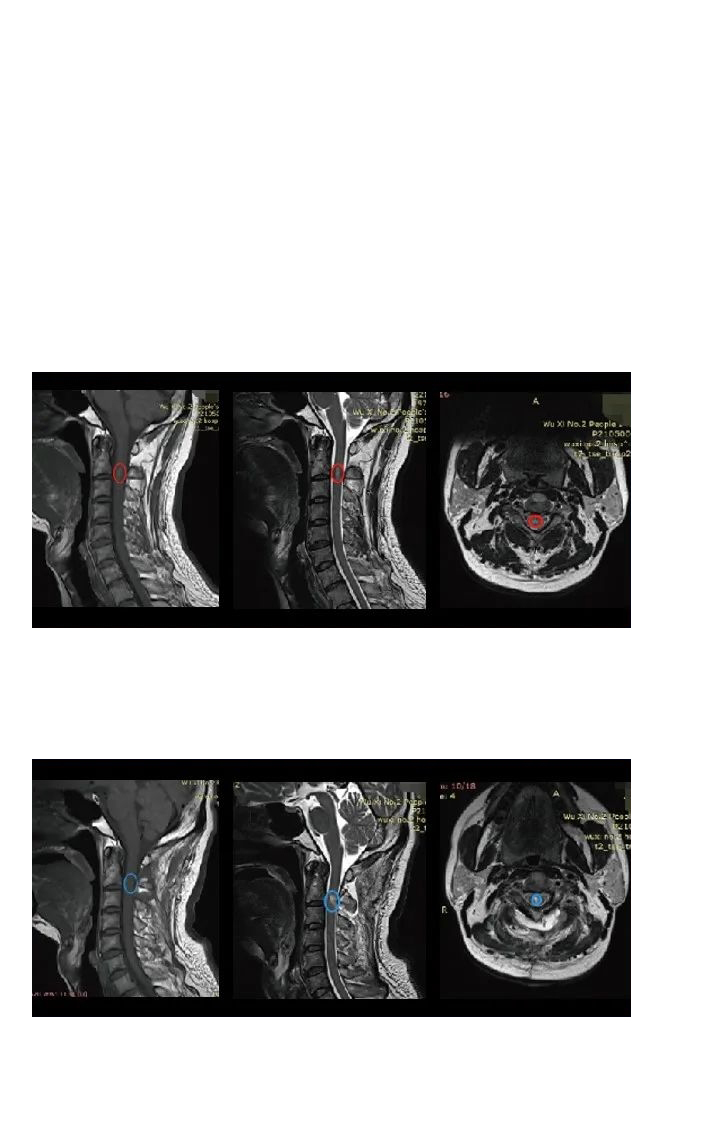

巴教授疑难手术案例:脊髓髓内肿瘤全切术后没有复发、无后遗症,行走自如!

50岁的刘先生,2年前因颈部及肩部疼痛就医检查出脊髓髓内肿瘤。由于肿瘤生长在高段颈髓内,被脊骨包围,手术暴露困难,术中脊髓稍受挤压损伤,就可能造成长期性瘫痪。很多医生都建议保守治疗。

但是,刘先生不愿意每天都生活在疾病的折磨中,坚持要找到更好的治疗方案。幸运的是,他后来从病友圈得知INC德国巴特朗菲教授2021年会在中国开展手术示范,于是通过INC国际神经外科医生集团,咨询到与巴教授进行咨询咨询和手术治疗的机会。

结合刘先生的既往病史和影像资料,巴教授表示:可以进行手术,且手术风险很低。如果术中明确病变是肿瘤,可以实现全切,但如果是炎症性病变,则仅切除一部分用于组织病理学诊断,再进行后续对症治疗。

手术当天,在术中神经电生理监测等高医疗设备辅助下,巴教授顺利全切肿瘤,病例诊断结果为室管膜瘤。术后3天刘先生就可以下地自如行走,术前症状大多已消失,术后无长期性并发症,也无需其他辅助治疗。术后1年INC回访刘先生时,他表示身体恢复良好,感谢巴教授给了他重获新生的机会。